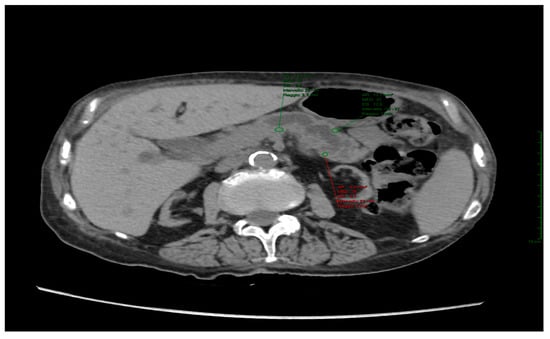

| Pancreatic Density | Fistula Present | No Fistula |

|---|---|---|

| Patients | 16 | 41 |

| Average | 27 | 33 |

| MIN | −17 | 10 |

| MAX | 51 | 51 |